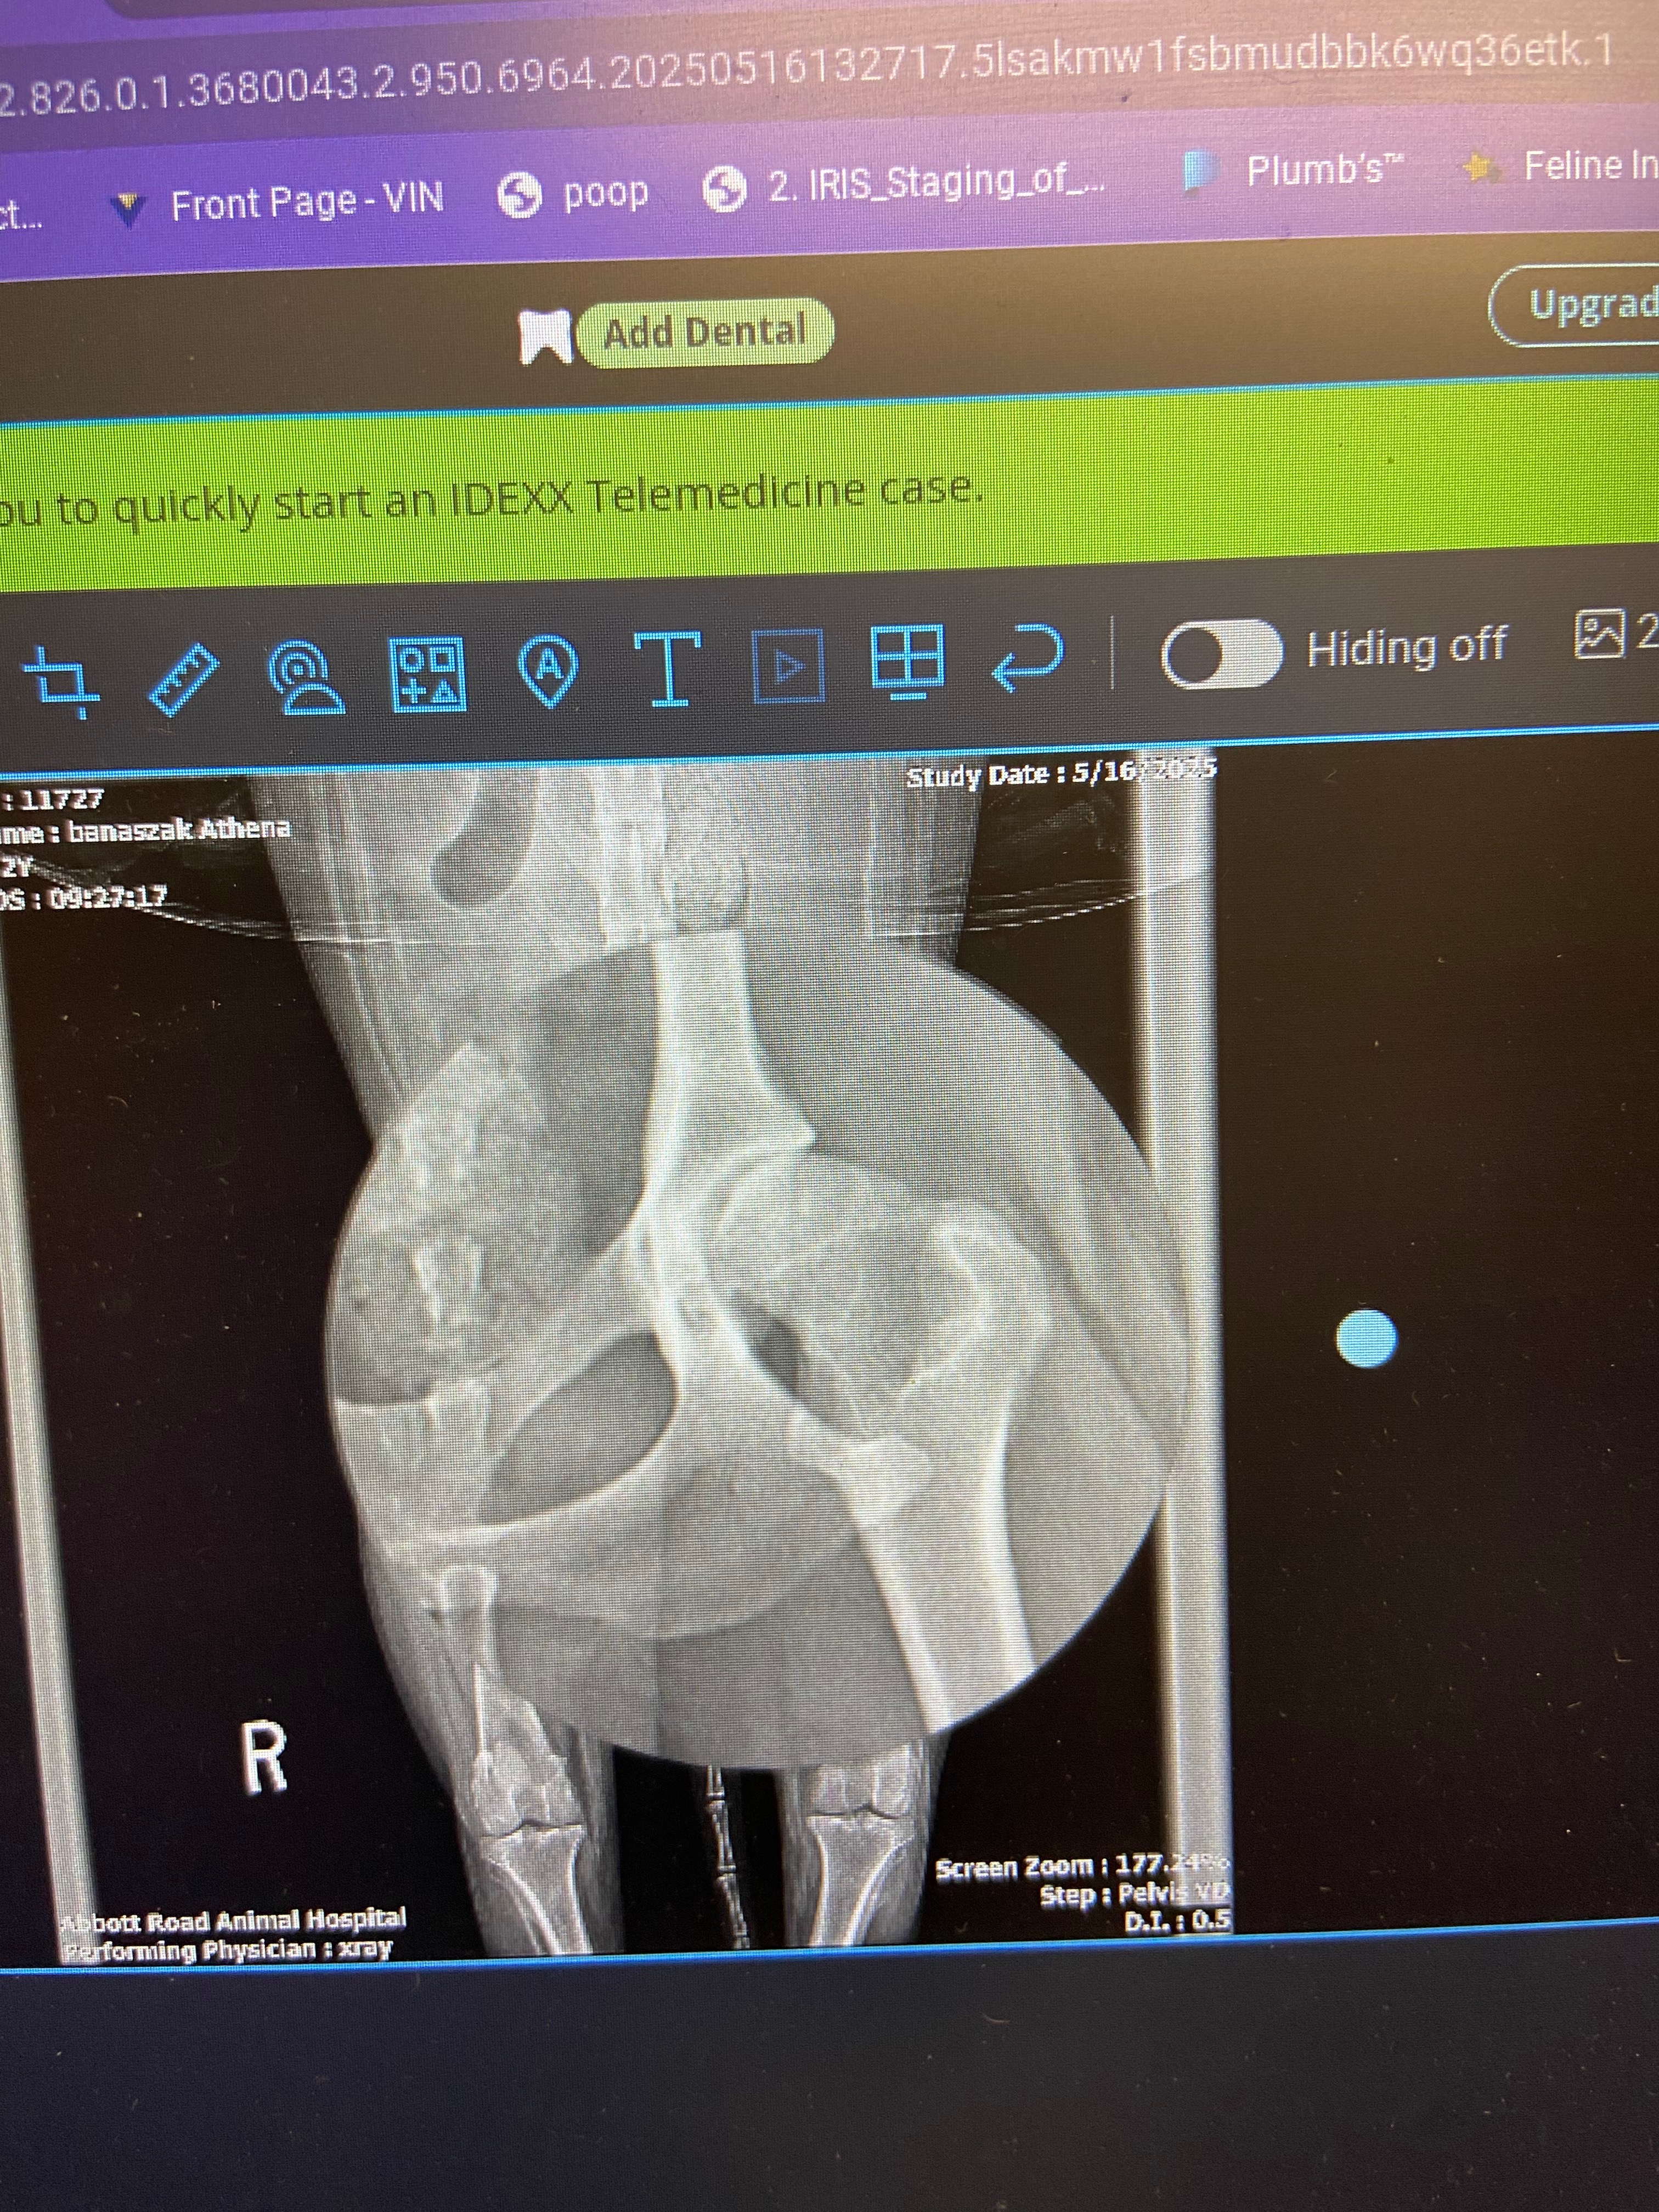

Athena is strong in her front end but very weak in the back. After walks or trips to the park, she struggles to get back up and often limps. A few times she doesn’t even want to stand up and will pull up her front end and drag her backside to reposition herself. At just two years old, this was heartbreaking to witness.

After a vet visit that included lab work and x-rays, the diagnosis was devastating: severe hip dysplasia in both hips, with the right side being significantly worse. The vet said her hips resemble those of a very old dog. Despite everything she’s been through already, she’s now facing a serious medical challenge.

Right now, Athena is on daily medication to manage her pain, but this is only a temporary solution. She urgently needs surgery: a full hip replacement on the right, and likely an FHO (femoral head ostectomy) on the left. At minimum, the right side needs to be addressed as soon as possible.